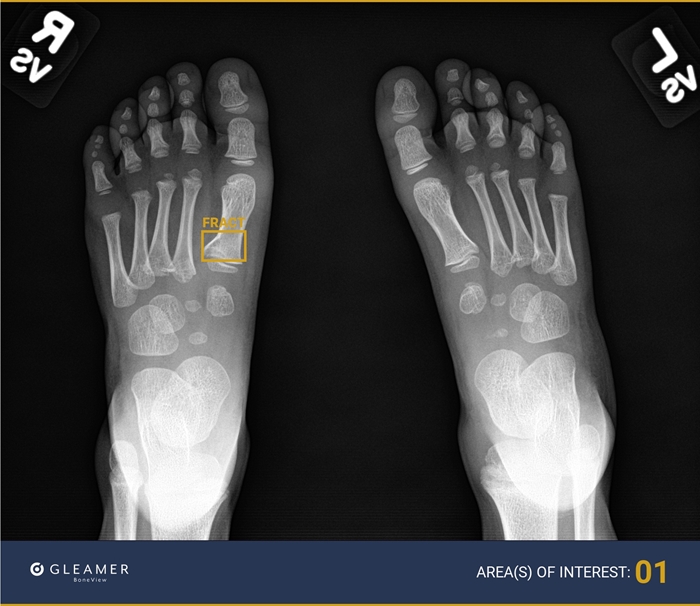

Gleamer BoneView AI identifies bone abnormalities, placing a yellow box around areas of concern in an image.

Trained on a massive database of X-ray images and powered by deep learning algorithms, Gleamer BoneView AI identifies bone abnormalities, placing a yellow box around areas of concern in an image. It is especially adept at identifying subtle signs of mild bone breaks such as buckle fractures.